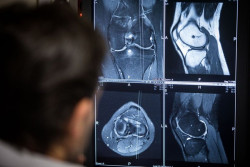

El reemplazo de rodilla, más doloroso para las mujeres posmenopáusicas con deficiencia de vitamina D

La vitamina D es una parte fundamental de una dieta saludable. Entre otros beneficios, se ha demostrado que protege contra las enfermedades óseas y mantiene la salud de los tejidos blandos. Un nuevo estudio sugiere que también puede desempeñar un papel en el grado de dolor postoperatorio que experimentan las mujeres posmenopáusicas después de someterse a un reemplazo total de rodilla, según publican en línea sus autores en `Menopause`, la revista de la Sociedad Norteamericana de Menopausia (NAMS, por sus siglas en inglés).